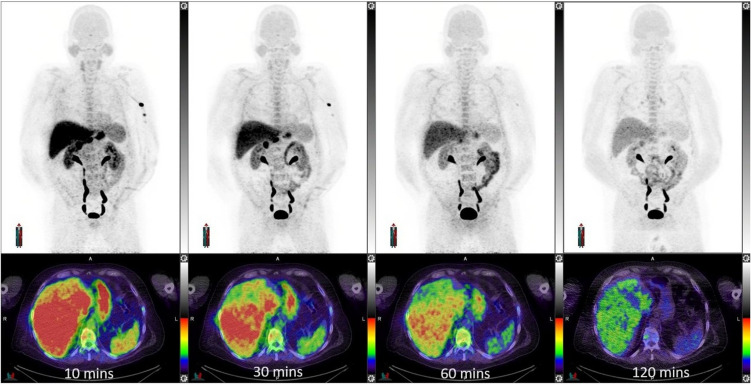

Results: Across the trial cohort, no adverse safety signals resulted from [18F]MEL050 administration. The whole-body effective dose was 0.0163 mSV/MBq for an adult male and 0.0206 mSV/MBq for an adult female. The human biodistribution was favorable with low uptake in organs at high risk of metastatic spread, including the brain. Of metastatic sites identified as melanoma on [18F]FDG PET/CT, only 31/65 (48%) were positive on [18F]MEL050 PET. Four [18F]FDG+[18F]MEL050+ metastases were resected from three patients and found to be melanotic by histological examination, whereas five [18F]FDG+[18F]MEL050- metastases from two patients were amelanotic. In our historical cohorts, amelanosis was more common in metastatic than primary disease (45% versus 20%) and the presence of melanin within sentinel lymph node metastases was associated with worse disease-free (HR 2.3 95% CI 1.3 - 4.3, p = 0.002) and disease-specific survivals (HR 3.6, 95% CI 1.4 - 9.7,p = 0.009) in stage III disease, compared with amelanotic sentinel lymph node metastases.